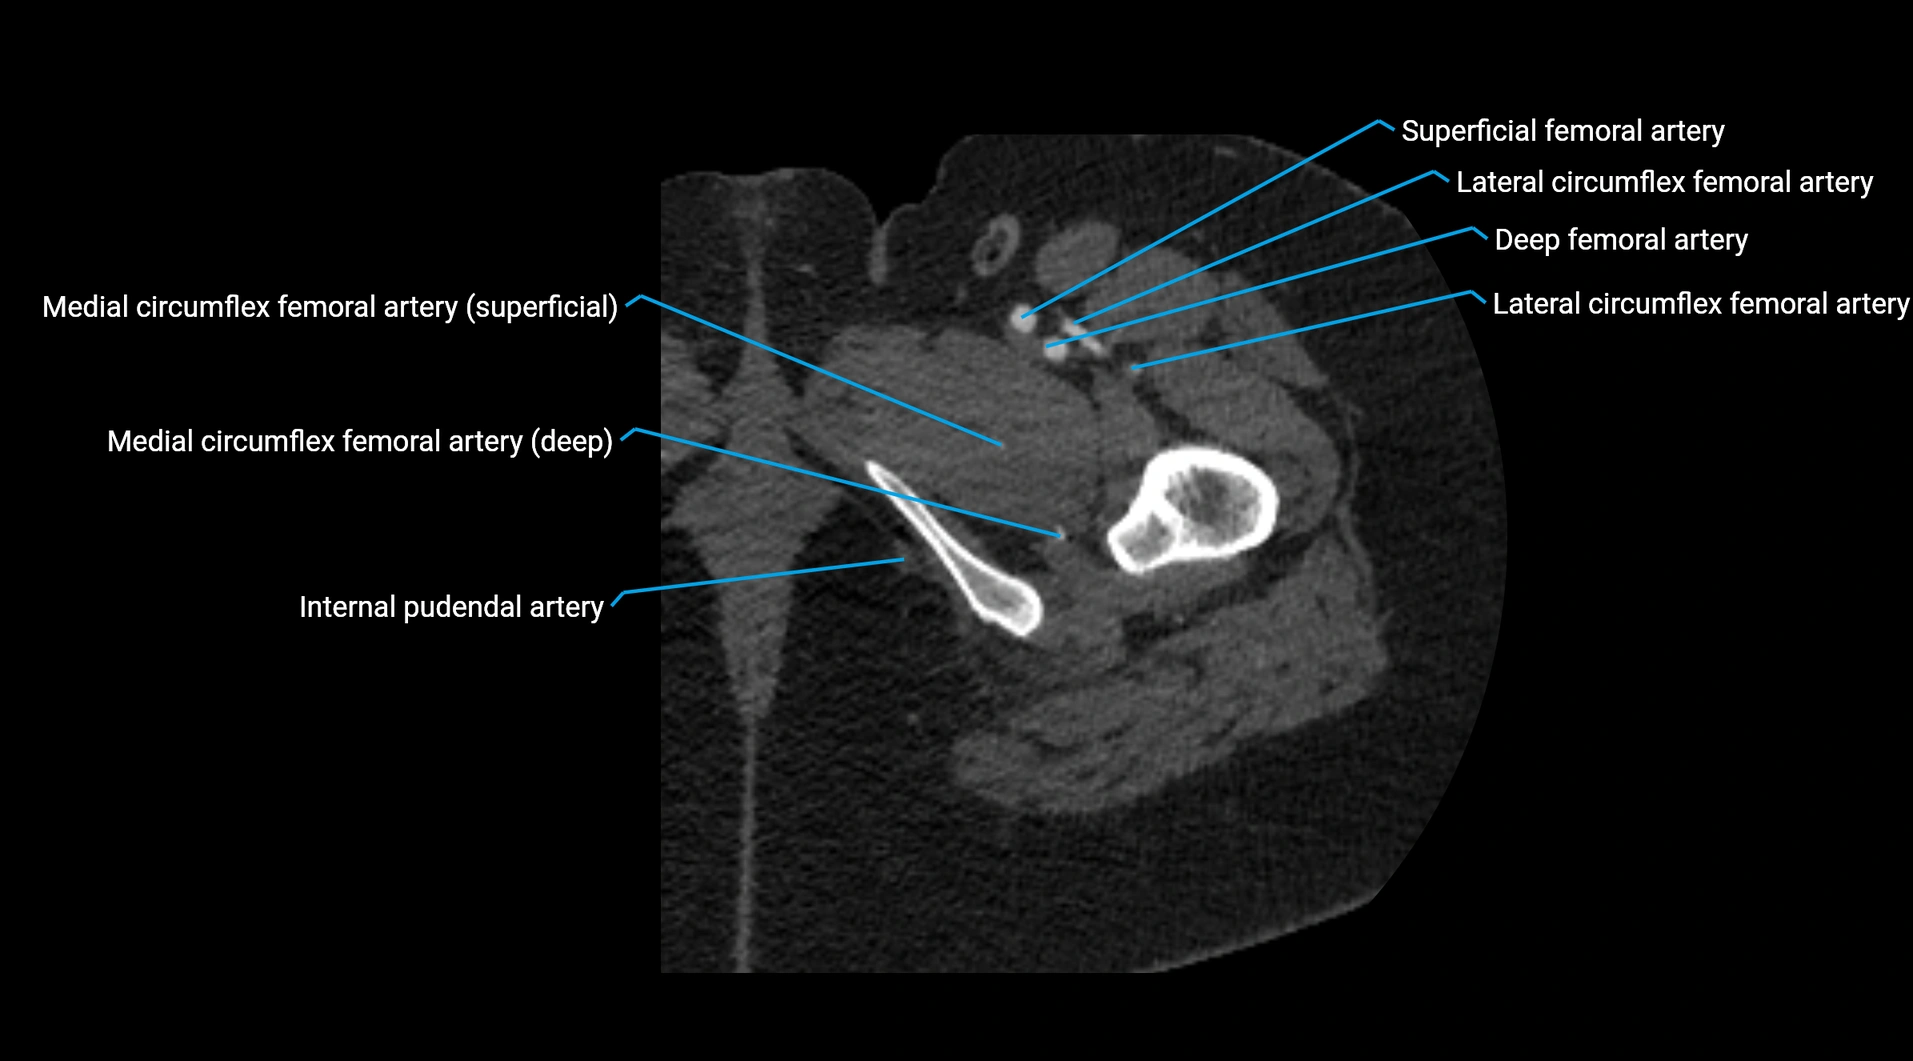

CT Appearance

Non-contrast CT:

• Appears as a tubular soft tissue structure anterior to vertebral bodies

• Calcified atherosclerotic plaques appear as hyperdense foci along the wall

• Useful for screening abdominal aortic aneurysm (AAA) size and mural calcification

Contrast-enhanced CT (CTA):

• Gold standard for abdominal aortic imaging

• Provides excellent detail of lumen, wall, aneurysm, thrombus, and branch vessels

• Multiplanar and 3D reconstructions help in aneurysm measurement, stent graft planning, and dissection evaluation

• Detects acute rupture, traumatic injury, or occlusion with high sensitivity